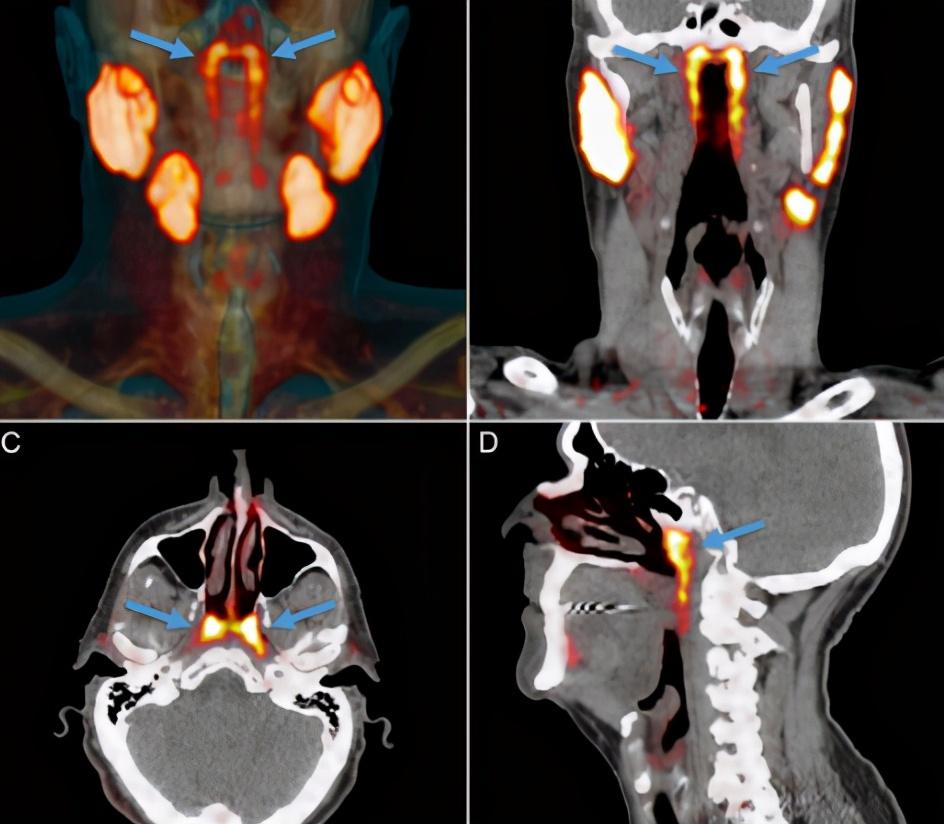

生物学在对癌细胞的研究过程中 , 偶然发现患者的咽喉深处有一对新器官 , 大小只有3.9厘米 , 是一对唾液腺 。 这一发现让研究小组大吃一惊 , 因为我们通常认为人类有三种大唾液腺 , 即腮腺、颌下腺和舌下腺 , 口腔和后喉粘膜还分布着1000多个小唾液腺 , 但从来不知道鼻腔后面还有一对 。

那么科学家是怎么发现它的呢?科学家在使用放射性示踪剂来追踪癌细胞 , 这种放射性示踪剂进入人体后 , 会与癌细胞中的PSMA结合 , 这实际上是癌细胞被标记的过程 。 结果科学家却发现 , PSMA不仅出现在了癌细胞上 , 还有一些分泌到了人的唾液腺中 , 在观看扫描成像的过程中就发现了这个唾液腺的位置 , 并将它命名为“管状腺” , 为了证明它确实是人类的器官 , 不是一种患者自己生成的无用组织 , 科学家又找了一百多个志愿者 , 发现他们的身上也有这个器官 , 这就说明它确确实实是每个人都拥有的重要器官 。